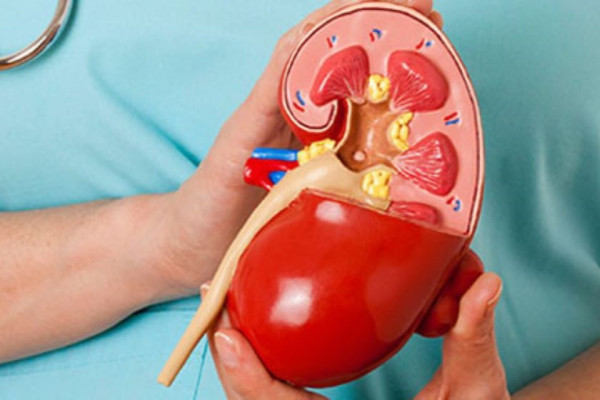

बुधबार विश्व मिर्गौला दिवस। नेपालमा पनि विभिन्न चेतनामूलक कार्यक्रम गरी मिर्गौला दिवस मनाइँदै छ। विश्व स्वास्थ्य संगठनले मार्च १० लाई विश्व मिर्गौला दिवसका रूपमा मनाउने घोषणा गरेसँगै नेपालमा पनि हरेक वर्ष यो दिवस मनाउन थालिएको हो। दिवसको यस वर्षको नारा ‘मिर्गौला रोग र बालबालिका, मिर्गौला रोग नियन्त्रणमा तत्काल सक्रिय बनौं’ रहेको छ।

मिर्गाैलाको उपचारको नेपालकै केन्द्र हो, भक्तपुर नगरपालिका वडा नं १ दूधपाटीस्थित सहिद धर्मभक्त राष्ट्रिय प्रत्यारोपण केन्द्रका कार्यकारी निर्देशक डा. कल्पनाकुमारी श्रेष्ठ उपचार गरे मिर्गाैला रोगको उपचार सम्भव भएको बताउँंछिन्। त्यसका लागि स्वस्थ मानिसले पनि वर्षमा न्यूनतम एकपटक मिर्गाैला परीक्षण गराउनुपर्ने उनी सुनाउँछिन्। धूमपानको आदत भएका, ५० वर्ष माथिका बयस्क र मिर्गौलामा समस्या भएकाहरूलाई मिर्गौला रोगको खतरा बढी हुने भएकाले ६ महिनामा एकपटक अनिवार्य रूपमा मिर्गौला परीक्षण गर्नुपर्ने उनी औंल्याउँछिन्। ‘मिर्गाैला रोग ट्राफिक जामजस्तै हो’, दिवसको पूर्वसन्ध्यामा बुधबार डा. श्रेष्ठले भनिन्, ‘जसरी ट्राफिक जाम भएपछि पछाडि फर्कन मिल्दैन र अगाडि नै बढ्नुपर्छ, त्यसरी नै मिर्गाैला रोग लागेपछि पछि सर्न नमिल्ने भएर त्यहींबाट मात्रै उपचार सुरु गर्नुपर्ने भएकाले रोग लागिसकेपछि नै पत्ता लगाउनुपर्छ। मिर्गौला रोगको शीघ्र पहिचान तथा र त्यसको समयमै निदान नै मिर्गौला स्वस्थ राख्ने मुख्य उपाय भएको उनी सुनाउँछिन्।

संसारभर १० प्रतिशत मानिस मिर्गौलासम्बन्धी समस्याबाट पीडित रहेको बताइन्छ। यसका आधारमा नेपालमा पनि कुल जनसंख्याको १० देखि १३ प्रतिशत करिब २७ लाख मानिसमा मिर्गौलासम्बन्धी समस्या भएको अनुमान गर्न सकिन्छ। यसमध्ये १० प्रतिशत अर्थात् दुई लाख ७० हजारको मिर्गौला बिग्रने गरेको छ भने प्रत्येक वर्ष तीन हजारको मिर्गौला पूर्ण रूपमा फेल हुने गरेको विश्व स्वास्थ्य संगठनले जनाएको छ।

केही वर्षयता संसारभर मिर्गौला रोगीको संख्या बढ्दै गएको छ। नेपाललगायतका बिकासोन्मुख मुलुकमा पनि मिर्गौला रोगीको संख्या चुनौतीपूर्ण रूपमा बढेको छ। मिर्गौला स्वस्थ्य राख्न हरेक दिन कम्तीमा तीन लिटर पानी पिउनुपर्छ, मधुमेह र उच्च रक्तचापलाई सन्तुलनमा राख्नुपर्छ।

मिर्गौला रोग लागिसकेपछि यसको उपचार महँगो भएकाले समयमै मिर्गौला परीक्षण गरी रोग निदान र उपचार गर्नु बुद्धिमानी हुन्छ।

विलासितापूर्ण जीवन जिउने र सुविधाभोगी जीवनशैलीले मोटोपनासँगै मिर्गौलाका समस्या बढ्दै गएकाले सन्तुलित खाना सरल जीवनशैली र पर्याप्त मात्रामा व्यायाम गर्नुपर्छ। बिहान वा बेलुका कम्तीमा ३० देखि ४५ मिनेट हिँडडुल गर्नु अनिवार्य रहेको चिकित्सकहरू बताउँछन्।

मिर्गौला उपचार सम्भव नभएपछि अर्को बिकल्पका रूपमा प्रत्यारोपण गर्नुपर्ने हुन्छ। नेपालमा मिर्गौला प्रत्यारोपणका लागि सामान्यतः साढे तीन लाखदेखि पाँच लाख रुपैयाँसम्म खर्च हुन्छ। प्रत्यारोपणका लागि मिर्गौलादाता आफ्नो नजिककै नाताबाट हुनुपर्छ, जुन सहज काम होइन। प्रत्यारोपण गरिसकेपछि खाने औषधि र प्रत्यारोपणअघिको डायलाइसिसको खर्चसमेत सामान्य नेपालीले धान्न सक्ने अवस्था छैन।

विश्व मिर्गौला दिवस हरेक वर्ष मार्च महिनाको दोस्रो बिहीबार मनाइन्छ। मिर्गौला स्वास्थ्यका बारेमा जनचेतना फैलाउन, रोगको समयमै पहिचान गर्न र बच्ने उपायहरूका बारेमा जानकारी दिन यो दिवस मनाइन्छ। नेपालमा पनि यो दिन विभिन्न सचेतनामूलक कार्यक्रम र स्वास्थ्य शिविर सञ्चालन गरी मनाइन्छ, जसमा मिर्गौला जोगाउने उपायमा बढी जोड दिइन्छ।